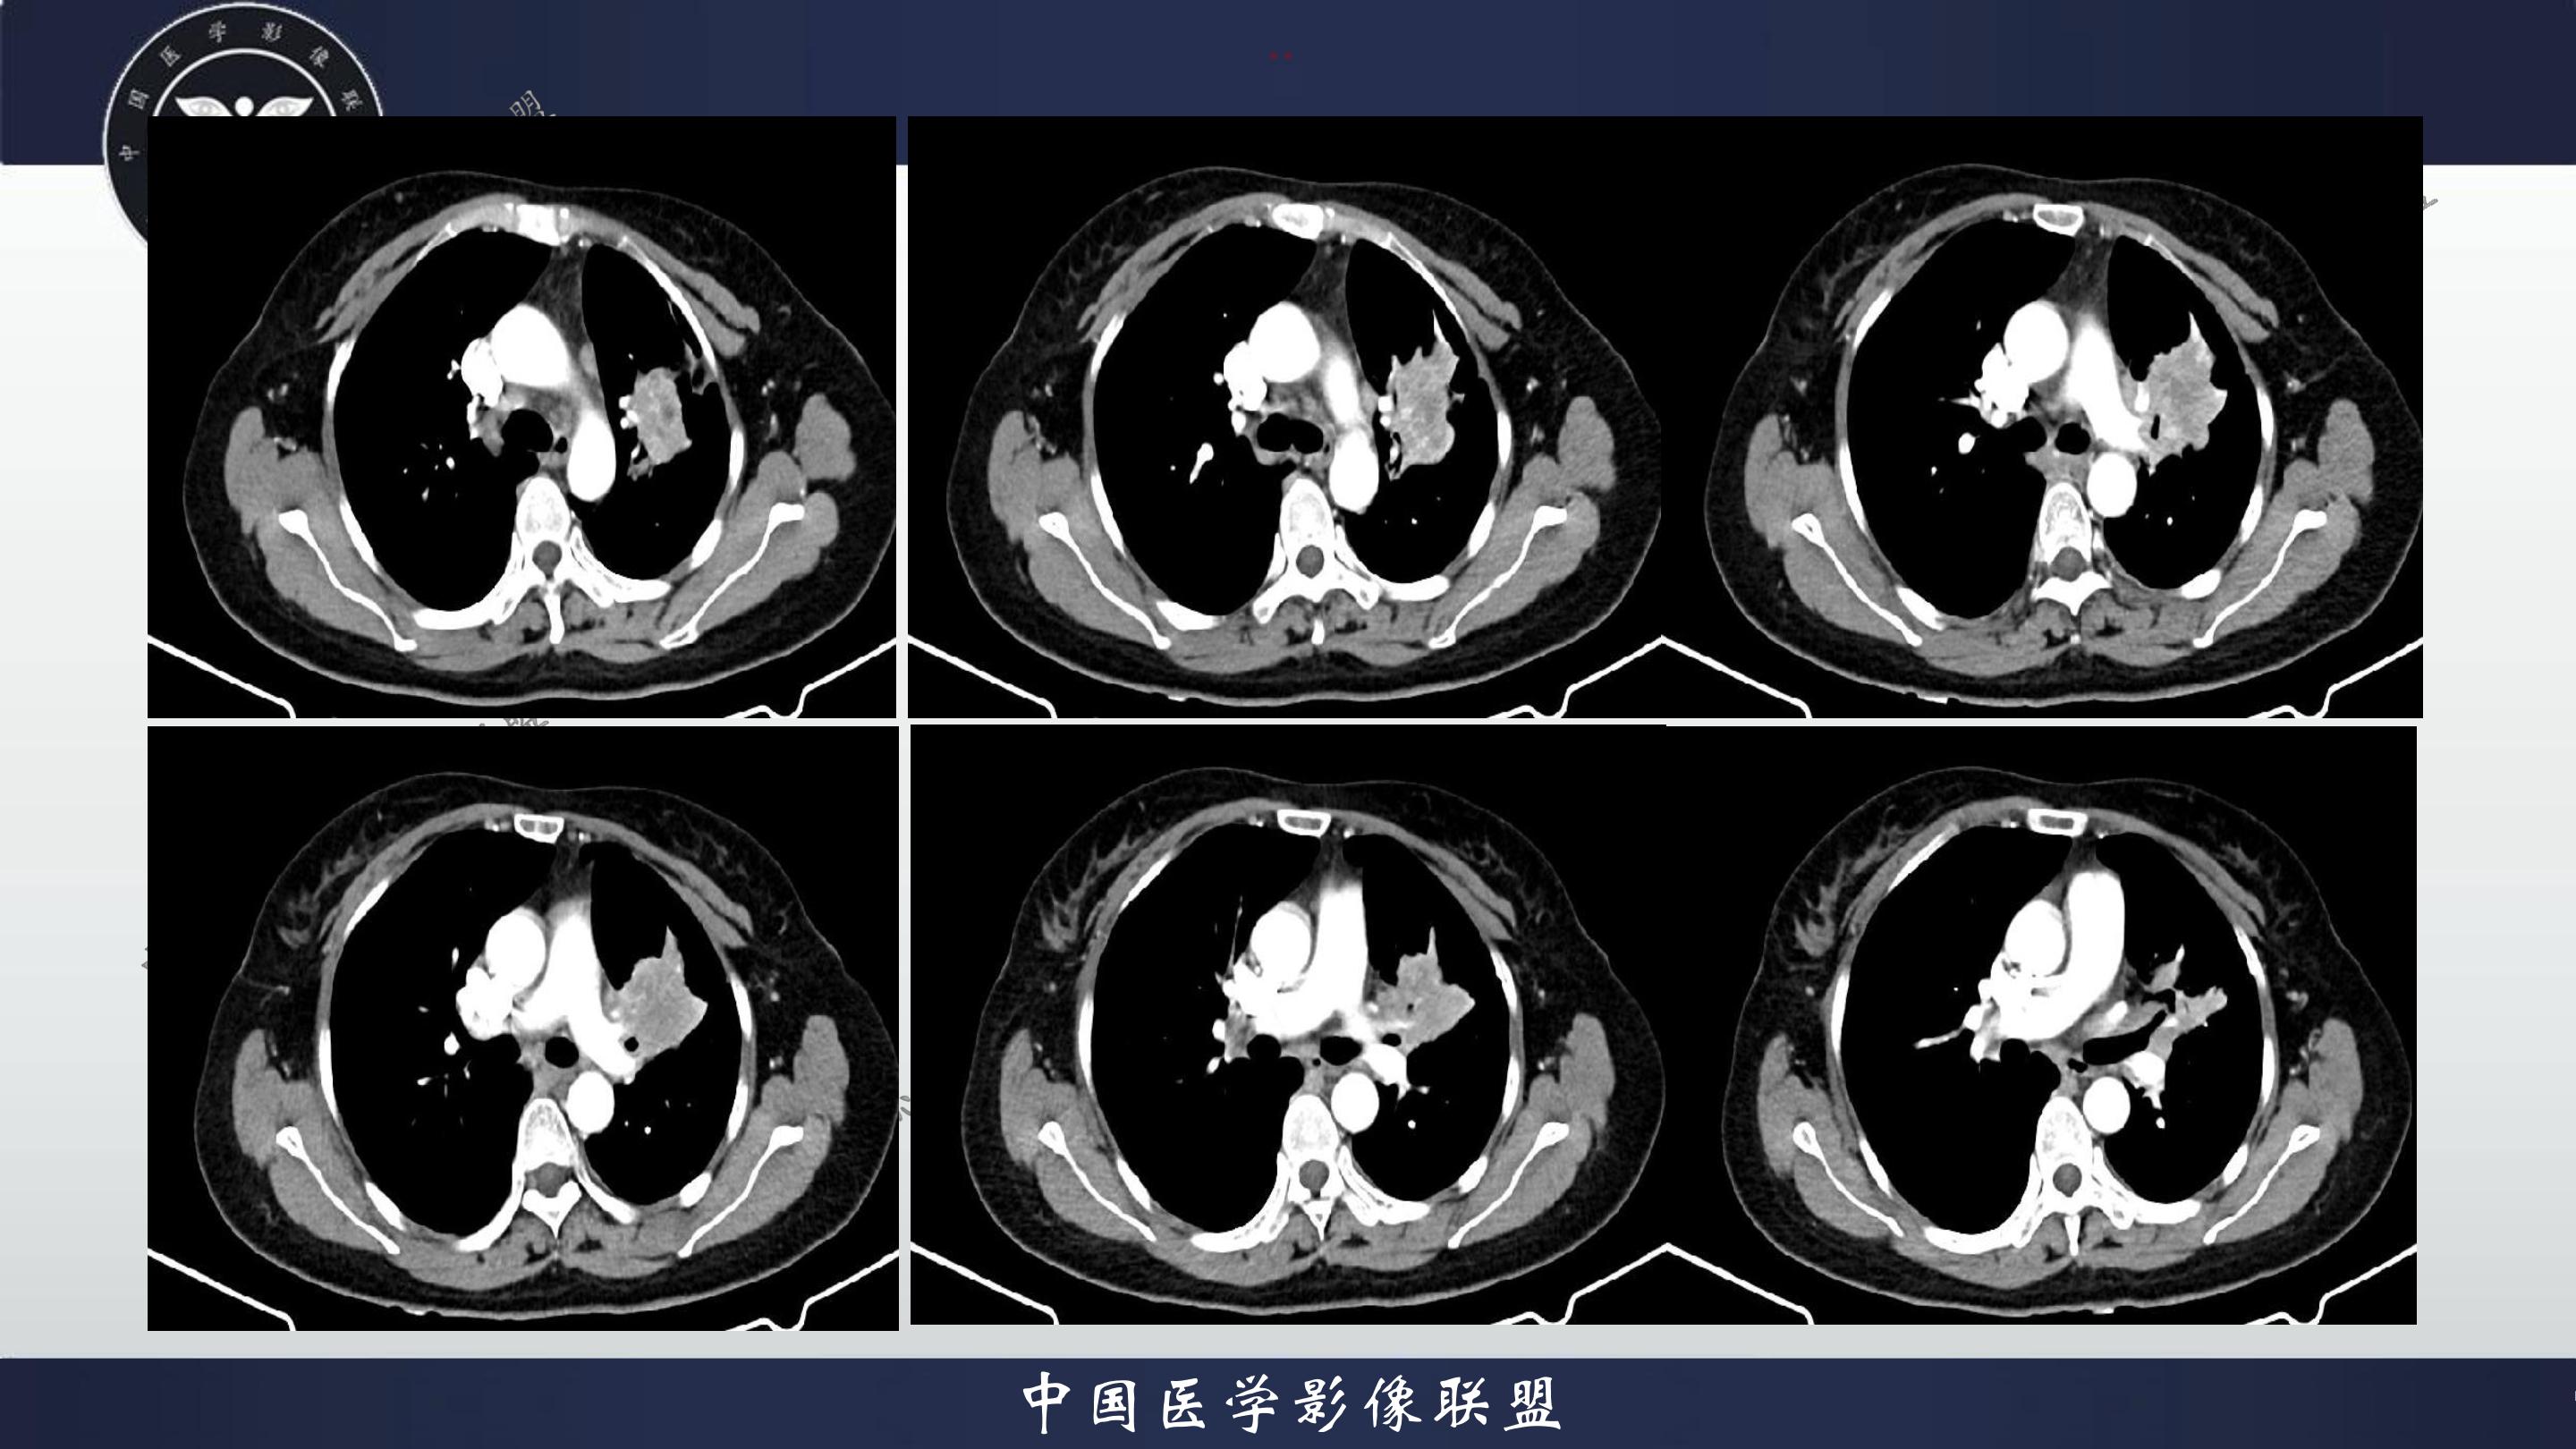

老年女性,咳嗽、咳痰伴痰中带血3月

3月前患者无明显诱因出现咳嗽、咳痰,呈阵发性咳嗽,咳大量黄色脓痰,痰不易咳出,伴痰中带血,量少,具体量不详,伴鼻塞、口干、乏力,活动后感喘息、劳累,休息后缓解,无发热、畏寒,无盗汗,无心慌、胸闷,无腹痛、恶心、呕吐,无头昏、心前区压榨性不适,院外予以输液及口服药物治疗后症状无明显缓解,现为系统诊治就诊我院门诊,门诊以“社区获得性肺炎”收入我科。病来精神、饮食、睡眠尚可,大小便正常,体重无明显变化。

既往有高血压病史10+年,血压最高160/70mmhg,自诉长期口服降压药物治疗,具体药物名称不详;8+年前患者有胆囊结石病史,自诉当时予以手术治疗后好转出院,具体不详;否认“糖尿病、冠心病"等疾病史。否认“肝炎、伤寒、结核”等传染病史;否认已知药物及食物过敏史,否认烟酒史

查体:T:36.8℃P:82次/分,R:20次/分,BP:135/82mmHg,spo2:96%.神清合作,咽稍充血,双侧扁桃体无肿大;双肺呼吸音粗,双肺可闻及少许湿性啰音,未闻及哮鸣音;心界不大,心率82次/分,律齐,心音低钝,各瓣膜听诊区未闻及杂音,腹软,中上腹压痛,无反跳痛及肌卫,肝脾未扪及。双下肢无水肿。

4.辅查:生化报告(2024-11-14 13:06:51)尿素氮或尿素:10.1mmol/L↑,尿酸:342umol/L↑,钾离子:3.16mmol/l↓,尿常规报告(2024-11-14 13:11:41)隐血:+2,凝血报告(2024-11-14 13:16:37)血浆D-二聚体测定:0.62ng/mL↑,生化报告单(2024-11-14 16:14:45)MP滴度(1:40):弱阳性,PCR报告(2024-11-14 16:50:37)人鼻病毒核酸(HRV-RNA)定性:阳性,传染性指标、粪便常规、BNP、心肌特异蛋白、CEA、肝功能、血脂、红细胞沉降率未见明显异常。血气分析回示:PH 7.443 PCO2 28.3mmhg PO2 90.9mmhg HCO3- 19.53mmol/L 氧和指数432.9mmhg;心电图回示:1.窦性心律2.T波改变(Ⅲ倒置、aVF低平)